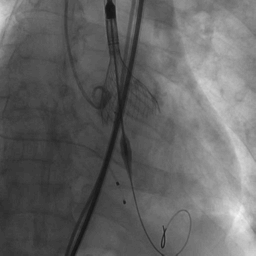

患者麻醉方式采取全麻,建立静脉通路后,穿刺左侧股动脉,建立副入路。采取右侧股动脉作为主入路,穿刺颈内静脉,然后经颈内静脉置入漂浮电极,临时起搏器入右室心尖。

跨瓣成功后,将Lunderquist导丝送入左心室,23 mm球囊预扩张,VenusA-Valve L29型号瓣膜精准定位并释放,术中造影及超声反馈良好,瓣膜形态良好,结果满意。